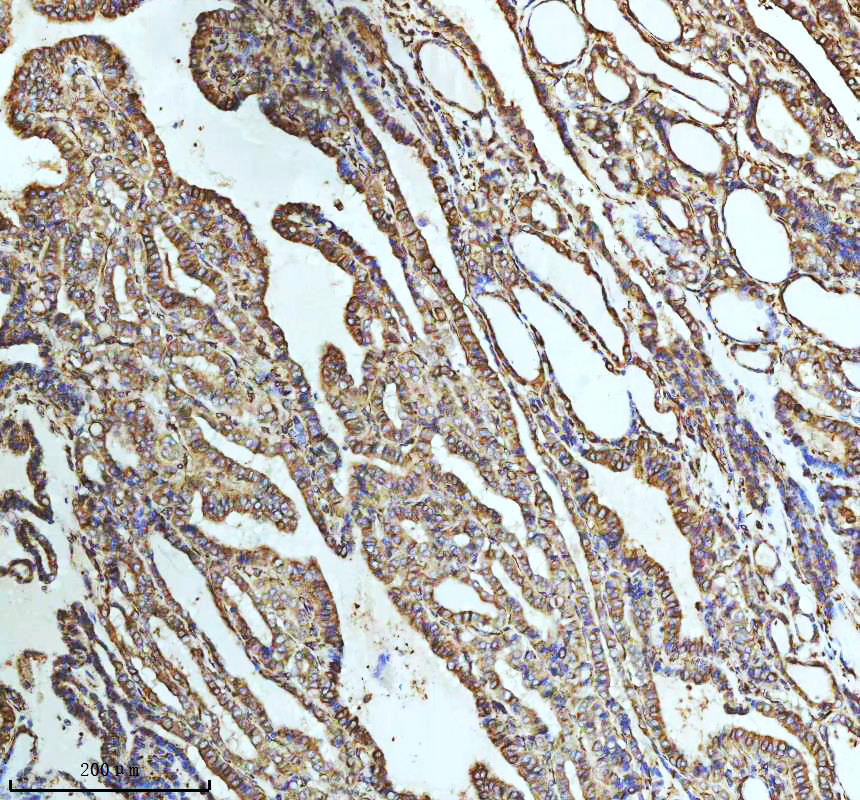

IHC analysis of beta I Tubulin/TUBB1 using anti-beta I Tubulin/TUBB1 antibody (BM3878) .

beta I Tubulin/TUBB1 was detected in a paraffin-embedded section of human placenta tissue. The tissue section was incubated with rabbit anti-beta I Tubulin/TUBB1 Antibody (BM3878) at a dilution of 1:200 and developed using HRP Conjugated Rabbit IgG Super Vision Assay Kit (Catalog # SV0002) with DAB (Catalog # AR1027) as the chromogen.